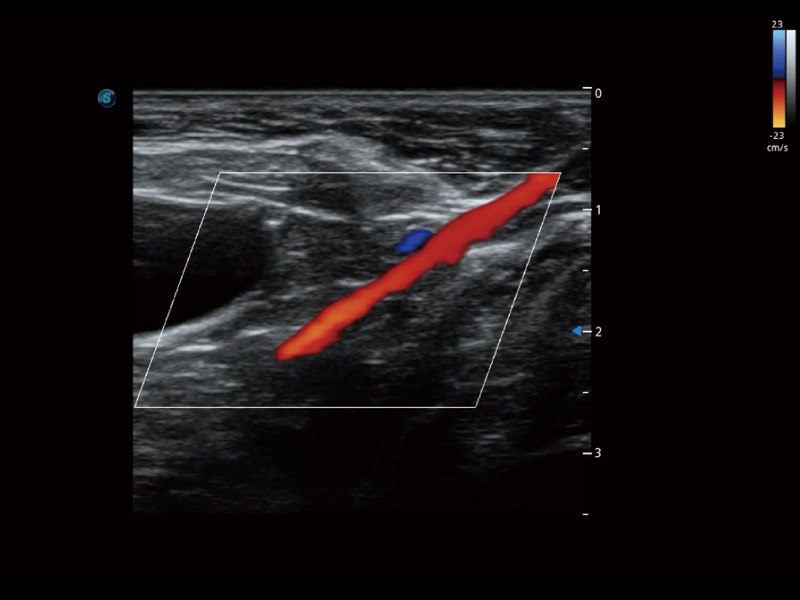

通过色彩血流和实时宽景相结合,可观察到完整的静脉或动脉的血流,方便医生检查。实时扫查过程中,如有任何操作失误也可以很容易地进行回扫擦除,而不会中断扫查。

为精细结构及组织边缘提供高清晰度的图像和更大的成像视野。帮助减轻医生的用眼疲劳,快速精准获得测量的数据。

增强穿刺针在动物解剖结构中的位置,提高穿刺介入的安全性和准确性。